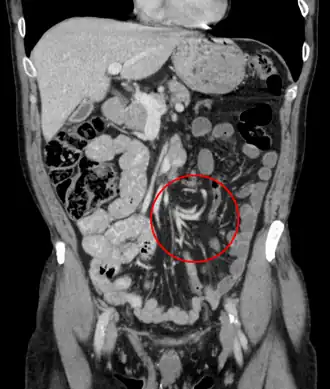

Корональная КТ органов брюшной полости, демонстрирующая заворот в виде скручивания кишечных петель

Заворот кишки — состояние, при котором петля кишечника закручивается вокруг себя и поддерживающей её брыжейки, что приводит к развитию кишечной непроходимости[1]. Симптомы включают боль в животе, вздутие живота, рвоту, запор и кровь в стуле[1][2]. Дебют симптомов может быть острым или постепенным[2]. Брыжейка может перекручиваться настолько туго, что прекращается приток крови к части кишечника и развивается ишемия кишечника[1]. В этой ситуации может появиться лихорадка или значительная боль при прикосновении к животу[2].

Факторы риска включают врожденный дефект, известный как неполный поворот кишечника, увеличение толстой кишки, болезнь Гиршпрунга и спайки брюшной полости[1]. Длительные запоры и диета с высоким содержанием клетчатки также могут увеличить риск[3]. Наиболее вовлекаемой частью кишечника у взрослых является сигмовидная кишка; на втором месте по степени поражения находится слепая кишка[1]. У детей чаще всего поражается тонкая кишка[5]. Также может пострадать желудок[6]. Диагноз обычно устанавливается с помощью медицинской визуализации, такой как снимки обзорной рентгенографии живота, серийная рентгеноскопия желудочно-кишечного тракта или компьютерная томография[1].